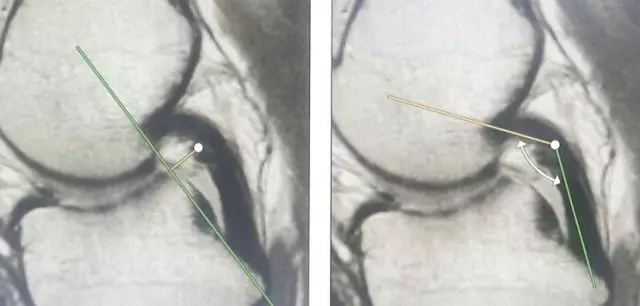

Blumensaat 角(-1.6度)

大于9-15度视为异常

前交叉韧带与胫骨平台角度(56度)

小于45-50度视为异常